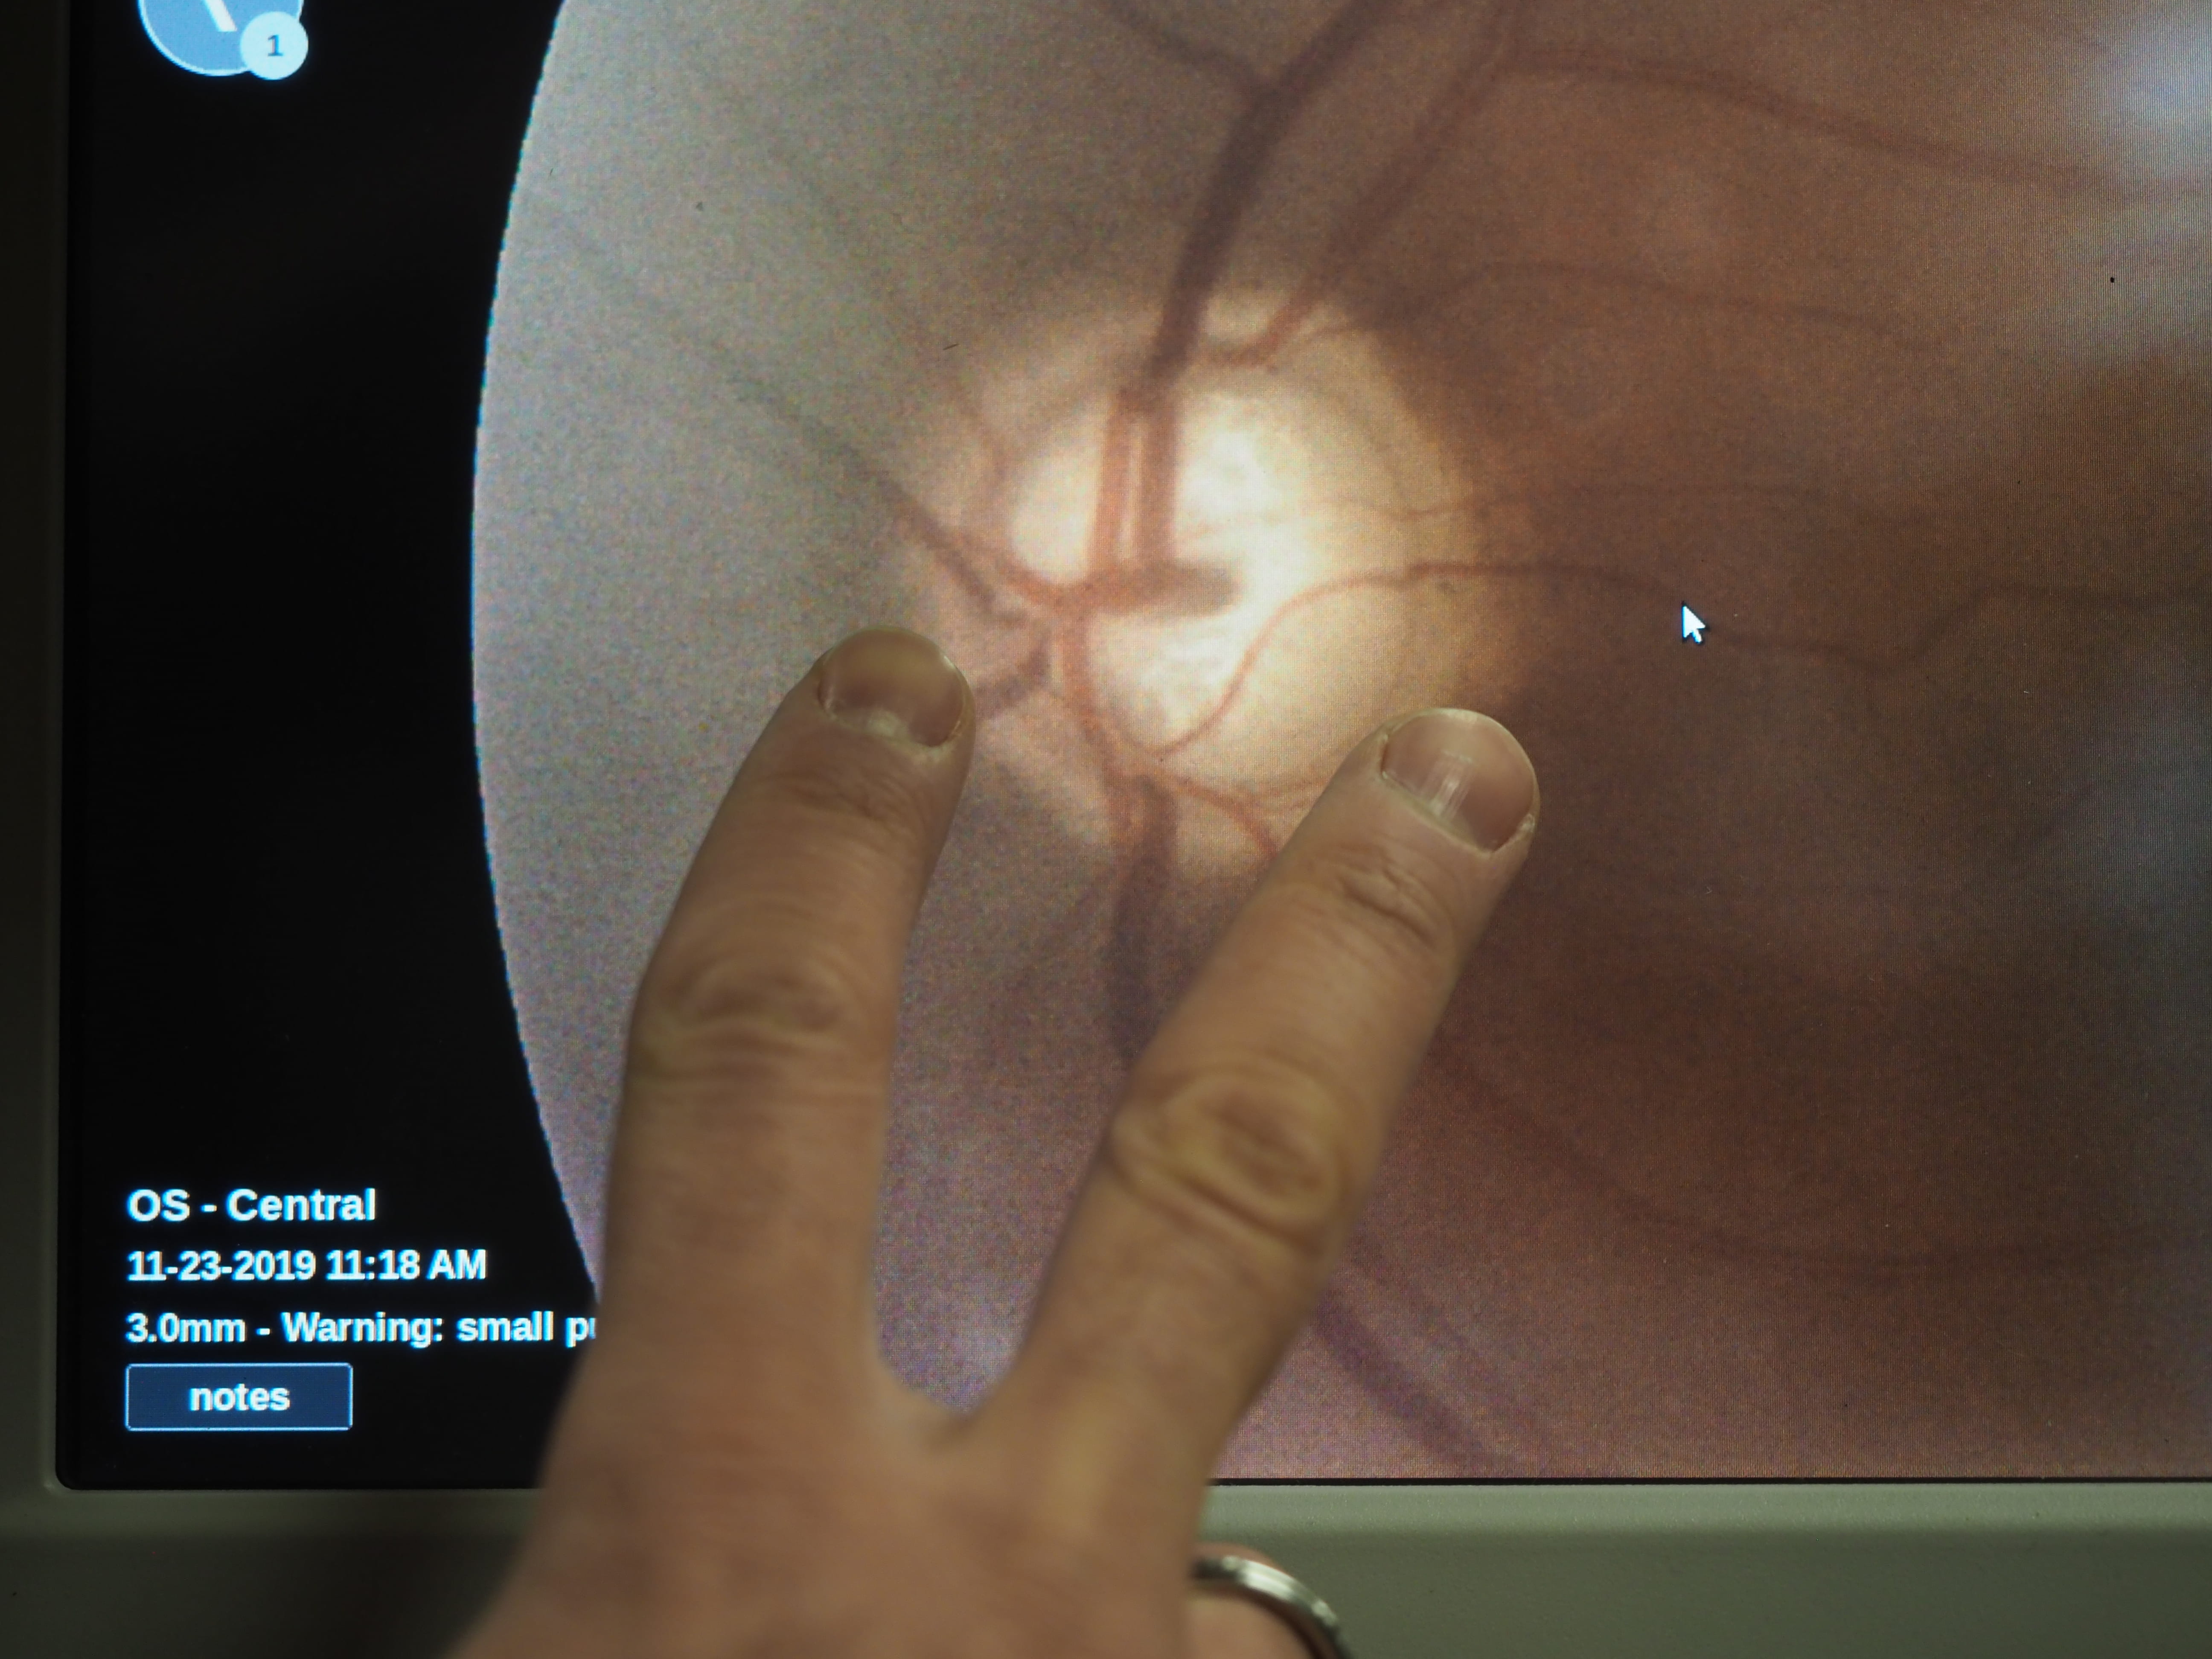

As a patient pressed their forehead against a sleek but intimidating piece of equipment known as a fundus camera, young people in scrubs crowded around to see the image generated by the machine.

It was clear, said a resident, who would deliver the official diagnosis: glaucoma.

The scan had shown damage to the optic nerve that, if left untreated, could cause irreversible vision loss and, eventually, blindness.